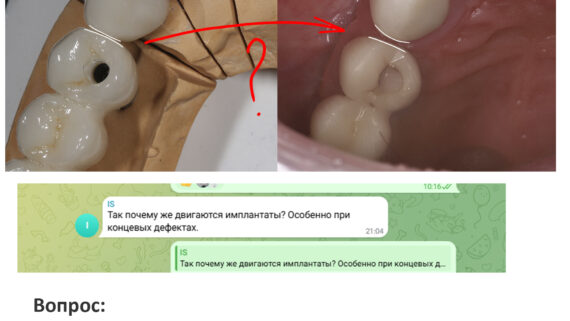

Это можно увидеть по прицельному снимку, который мы сделали через 3 месяца после остеопластики:

Вспомните, как стояли винты сразу после операции и как они выглядят сейчас.

Обратите внимание на появление новообразованной костной ткани под блоком — на снимке наглядно прослеживается ее губчатая структура. Пока границы слоев костной ткани видны хорошо, но, в дальнейшем, они почти исчезнут.

Пациентка озвучила свое решение по поводу количества имплантов — мы решили установить пока два импланта в область 35, 37 зубов, сделать на них мостовидный протез. Если вдруг по каким-то причинам он ее не устроит — мы всегда можем доставить имплантат 36 зуба и сделать три одиночные коронки. Без проблем — костной ткани теперь достаточно.

Снимок после проведенной имплантации:

Винты, фиксировавшие блок, удалены. Имплантаты позиционированы по разметке ортопеда, исходя из планируемой ортопедической конструкции.